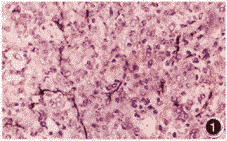

标本连续石蜡切片,分别做HE及免疫组化染色。第一抗体用第Ⅷ因子相关抗原(FⅧRAg)显示肿瘤新生血管,用增殖细胞核抗原(PCNA)反映瘤细胞增殖活性。将FⅧRAg染色阳性的单个内皮细胞或一簇内皮细胞作为一个微血管(图1),每张切片选2个血管密度最多的肿瘤区域,在高倍镜(200倍)下先后计数2次,其微血管数平均值即MVD值。PCNA阳性染色定位于细胞核内(图2),随机观察10个高倍视野(400倍),阳性细胞占所有计数细胞的百分比即PCNA增殖指数。同组间肿瘤MVD的比较采用t检验;肿瘤MVD和PCNA增殖指数的相关性采用直线相关分析。

图1 骨巨细胞瘤,第Ⅷ因子相关抗原免疫组化染色显示瘤组织内的新生微血管 SP法×200 图2 骨巨细胞瘤,PCNA阳性物质定位于肿瘤单核基质细胞核内 SP法×400